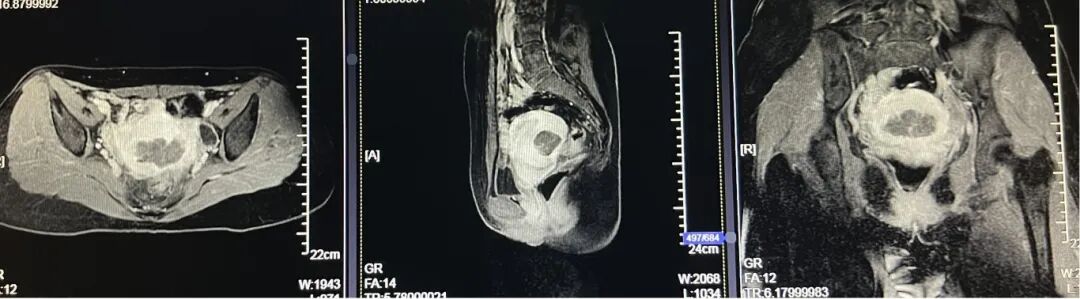

患者女,28岁,2021-06-07于青岛市妇女儿童医院就诊。 主诉:进行性痛经加重3年余。 现病史:患者月经初潮即有经期下腹痛,无需口服止痛药物。3年前痛经渐进性加重,目前经期腹痛VAS评分8分,伴恶心呕吐、肛周坠胀感。伴有非经期腹痛,VAS评分4分,持续4-5天,有深部性交痛。月经周期、经期及经量较前无明显改变。我院就诊超声提示:子宫后壁探及低回声结节,大小46mm*56mm*42mm,考虑子宫肌瘤。患者有明确生育要求,为求进一步治疗,门诊以“子宫腺肌病?子宫肌瘤?”收入院。患者自发病以来,神志清,精神可,饮食正常,经期夜间睡眠欠佳,体重较前无明显增减。 既往史:体健,否认慢性病及传染性疾病病史,否认外伤史,否认输血史,否认食物、药物过敏史。 月经及婚育史:既往月经规律,周期28-30天,经期5-6天,末次月经:2021-05-24。G1P0A1,2021年4月孕11周“稽留流产”行药物流产1次。 家族史:无特殊。 体格检查:T36.2℃,P77次/分,R18次/分,BP101/67mmHg,身高160cm,体重56kg。疼痛评分:0分。心、肺、腹部查体无异常。 专科查体: 妇科查体:外阴发育正常,阴道畅,宫颈光滑,子宫后位,增大如孕2月,固定、活动差,无压痛,双侧附件区未及异常。三合诊:左侧骶韧带触及触痛结节。 辅助检查: 2021-06-03 B超:子宫后位,宫体大小正常,形态规则,肌层内回声欠均匀,后壁肌层探及低回声结节,大小约46mm*56mm*42mm,边界清。宫腔内膜受压前移,厚10.1mm。宫颈形态正常。左侧卵巢探及液性暗区,大小约39mm*29mm,透声好,右侧卵巢大小正常。右侧附件区未见明显异常。 2021-06-07 肿瘤指标:糖类抗原CA19-9 52.21U/ml;糖类抗原CA125 112.9U/ml ↑; 2021-06-07 MRI提示:子宫后壁子宫腺肌病、盆腔子宫内膜异位症? 初步诊断: 2.盆腔子宫内膜异位症 3.不良孕产史 1.2021-06-08在镇静镇痛下行聚焦超声消融手术(FUAS)治疗。术后增强核磁检查提示子宫后壁腺肌病灶内无灌注区,子宫内膜及浆膜血流灌注正常。 2.2021-06-22术后第一次月经来潮,痛经较前减轻,VAS评分2-3分。术后辅助GnRh-a治疗3周期辅助治疗,同时口服钙片补钙治疗,用药期间闭经,无腹痛等不适。 3.GnRh-a治疗3周期后,2021-09-08复查B超:子宫后位,宫体大小正常,形态规则,肌层内回声欠均匀,后壁肌层探及高回声团,大小约38mm*37mm*26mm,边界清,内见少许血流信号。宫腔内膜受压前移,厚4.1mm。宫颈形态正常。双侧卵巢大小正常。双侧附件区未见明显异常。 4.2021-11-22月经复潮,经量正常,痛经VAS 2分,月经第5天开始口服地屈孕酮20mg QD,每月经周期20天,建议试孕半年。 5.2022-04-27随访复查,LMP:2022-02-24,停经9周,B超:子宫后位,体积增大,形态饱满,被膜光滑,后壁肌层回声不均匀,内见低回声区,较大范围约35mm*26mm,宫腔内见大小约32mm*31mm*24mm妊娠囊,张力可,内见胎芽,纵径22.4mm,心管搏动规律,妊娠囊下方探及不规则液性暗区,范围约21mm*8mm。双侧附件区未见明显异常。继续口服地屈孕酮10mg q8h保胎治疗。孕期进展顺利,2022-11-25外院足月剖宫产1女婴,体重3300g,Apgar评分10分-10分。 子宫内膜异位症和子宫腺肌病是妇科常见疾病。除了引起疼痛和月经改变,越来越多的证据表明,这两种疾病对女性的生殖功能有重要影响。临床可表现为不孕不育和流产等,尤其是早期流产[1]。 本例患者B超提示“子宫肌瘤”可能,但后续评估更符合子宫腺肌病。弥漫性子宫腺肌病的超声检查准确性较高,但子宫腺肌瘤超声表现与子宫肌瘤相似,临床诊断需要结合患者的症状、CA125水平综合判断。相比超声,磁共振检查对子宫腺肌病的分型更有优势,也更容易发现合并的盆腔子宫内膜异位症。后位子宫的后壁腺肌病灶往往合并子宫直肠陷凹的内异病灶,本例患者即属于该情况,治疗策略应兼顾两种疾病并同时考虑患者的生育需求。 针对子宫腺肌病,传统的病灶切除手术对子宫损伤较大,合并盆腔子宫内膜异位症时,手术操作也较困难,所以对于有生育需求的患者选择手术治疗需要相当慎重。聚焦超声消融术(HIFU)可选择性消融子宫腺肌病病灶、使病灶缩小,同时保护子宫完整性,从而达到减轻症状、缩小病灶、改善生育的目的[2]。但无法同时消融盆腔子宫内膜异位病灶,需要联合药物综合治疗。 子宫腺肌病和子宫内膜异位症的慢病管理理念已逐渐被认可,药物治疗是基石。而目前一线用药促性腺激素释放激素激动剂、地诺孕素等均会抑制排卵,有生育需求的患者备孕时需要停药。而停药后的试孕期病灶复发和进展风险较高,从而影响妊娠几率。地屈孕酮10-20mg/d可缓解内异症痛经,不抑制排卵,兼顾子宫腺肌病和盆腔子宫内膜异位症患者的治疗和备孕。此外,对于疑有黄体功能不足者黄体期使用地屈孕酮还可能提高自然受孕率,备孕期周期性用药副作用低,安全性高。 子宫腺肌病不仅可导致患者的生育力低下,诸如排卵障碍、不孕、流产、早产、死产、胎儿生长受限等,还可导致妊娠期母亲并发症如剖宫产率增加、子痫前期、前置胎盘及胎盘早剥等[3],一旦妊娠应更加积极的给予保胎治疗和严密随访,积极补充孕酮以抑制子宫平滑肌收缩,尽可能提高活产率。 子宫腺肌病和子宫内膜异位症具有类似的发病机制,也常常合并存在,严重影响女性的生殖健康。针对两种疾病的治疗应规范化、个体化、微创化。给予规范用药或手术治疗,减灭和消除病灶,减轻临床症状的同时,应充分考虑患者的主要诉求、年龄和生育需求,尽可能选取创伤小的治疗方式。重视患者全生命周期的管理,早诊早治、促进生育、长期管理预防复发,避免反复手术带来的创伤,定期随访,警惕恶变。 该患者28岁,痛经伴非经期腹痛,临床诊断符合子宫腺肌瘤合并子宫内膜异位症。既往不良孕产史,有明确生育需求,具有治疗指征。针对后壁子宫腺肌瘤传统手术方式对子宫损伤较大不利于患者后续妊娠,康医生选择了聚焦超声消融术治疗缩小子宫腺肌病病灶,减轻患者痛经并改善子宫形态,有利于提高妊娠几率。 子宫腺肌病和子宫内膜异位症在年轻患者中复发几率极高,可谓“不死的癌症”,当患者又有生育需求时,如何兼顾治疗和生育确实给我们提出了较高的要求。该患者在停用GnRh-a后月经来潮,备孕期间给予口服地屈孕酮稳定病灶、改善痛经,同时不会影响下丘脑-垂体-卵巢轴(HPO轴)而抑制排卵,还能提高自然受孕几率,可谓一举两得。 患者服用地屈孕酮3个月后便顺利妊娠,体现了治疗的有效性。更难能可贵的是,康医生重视子宫腺肌病患者的孕期管理,妊娠后继续给予口服地屈孕酮积极保胎,抑制子宫平滑肌收缩,也体现了将子宫腺肌病患者作为高危孕产妇管理的治疗理念。 参考文献: